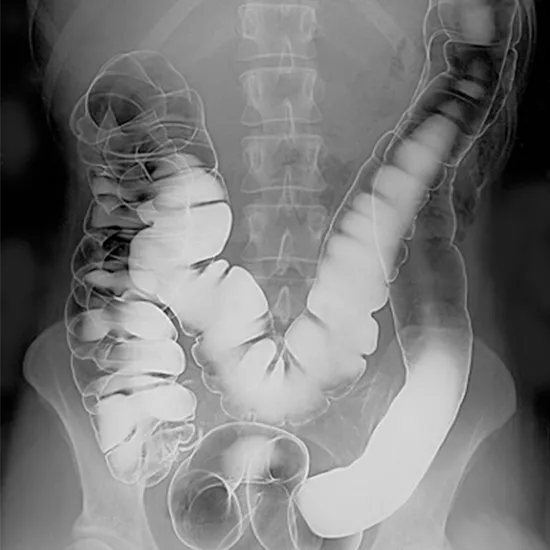

The Barium Enema Double-Contrast is also known as DCBE.  It utilizes X-rays to assess the conditions of the colon and detect abnormal growths in the colon. On the X-ray, Barium(silver-white metallic compound) is used for outlining the colon and rectum for better and easy visualization of the problem.

• To diagnose colorectal cancer at the earliest stage and inflammatory disease

• To detect polyps, diverticulum, and structural modifications in the large intestine.

• Detect lesions in the entire colon and abnormalities in the wall of the intestine such as narrowed areas.